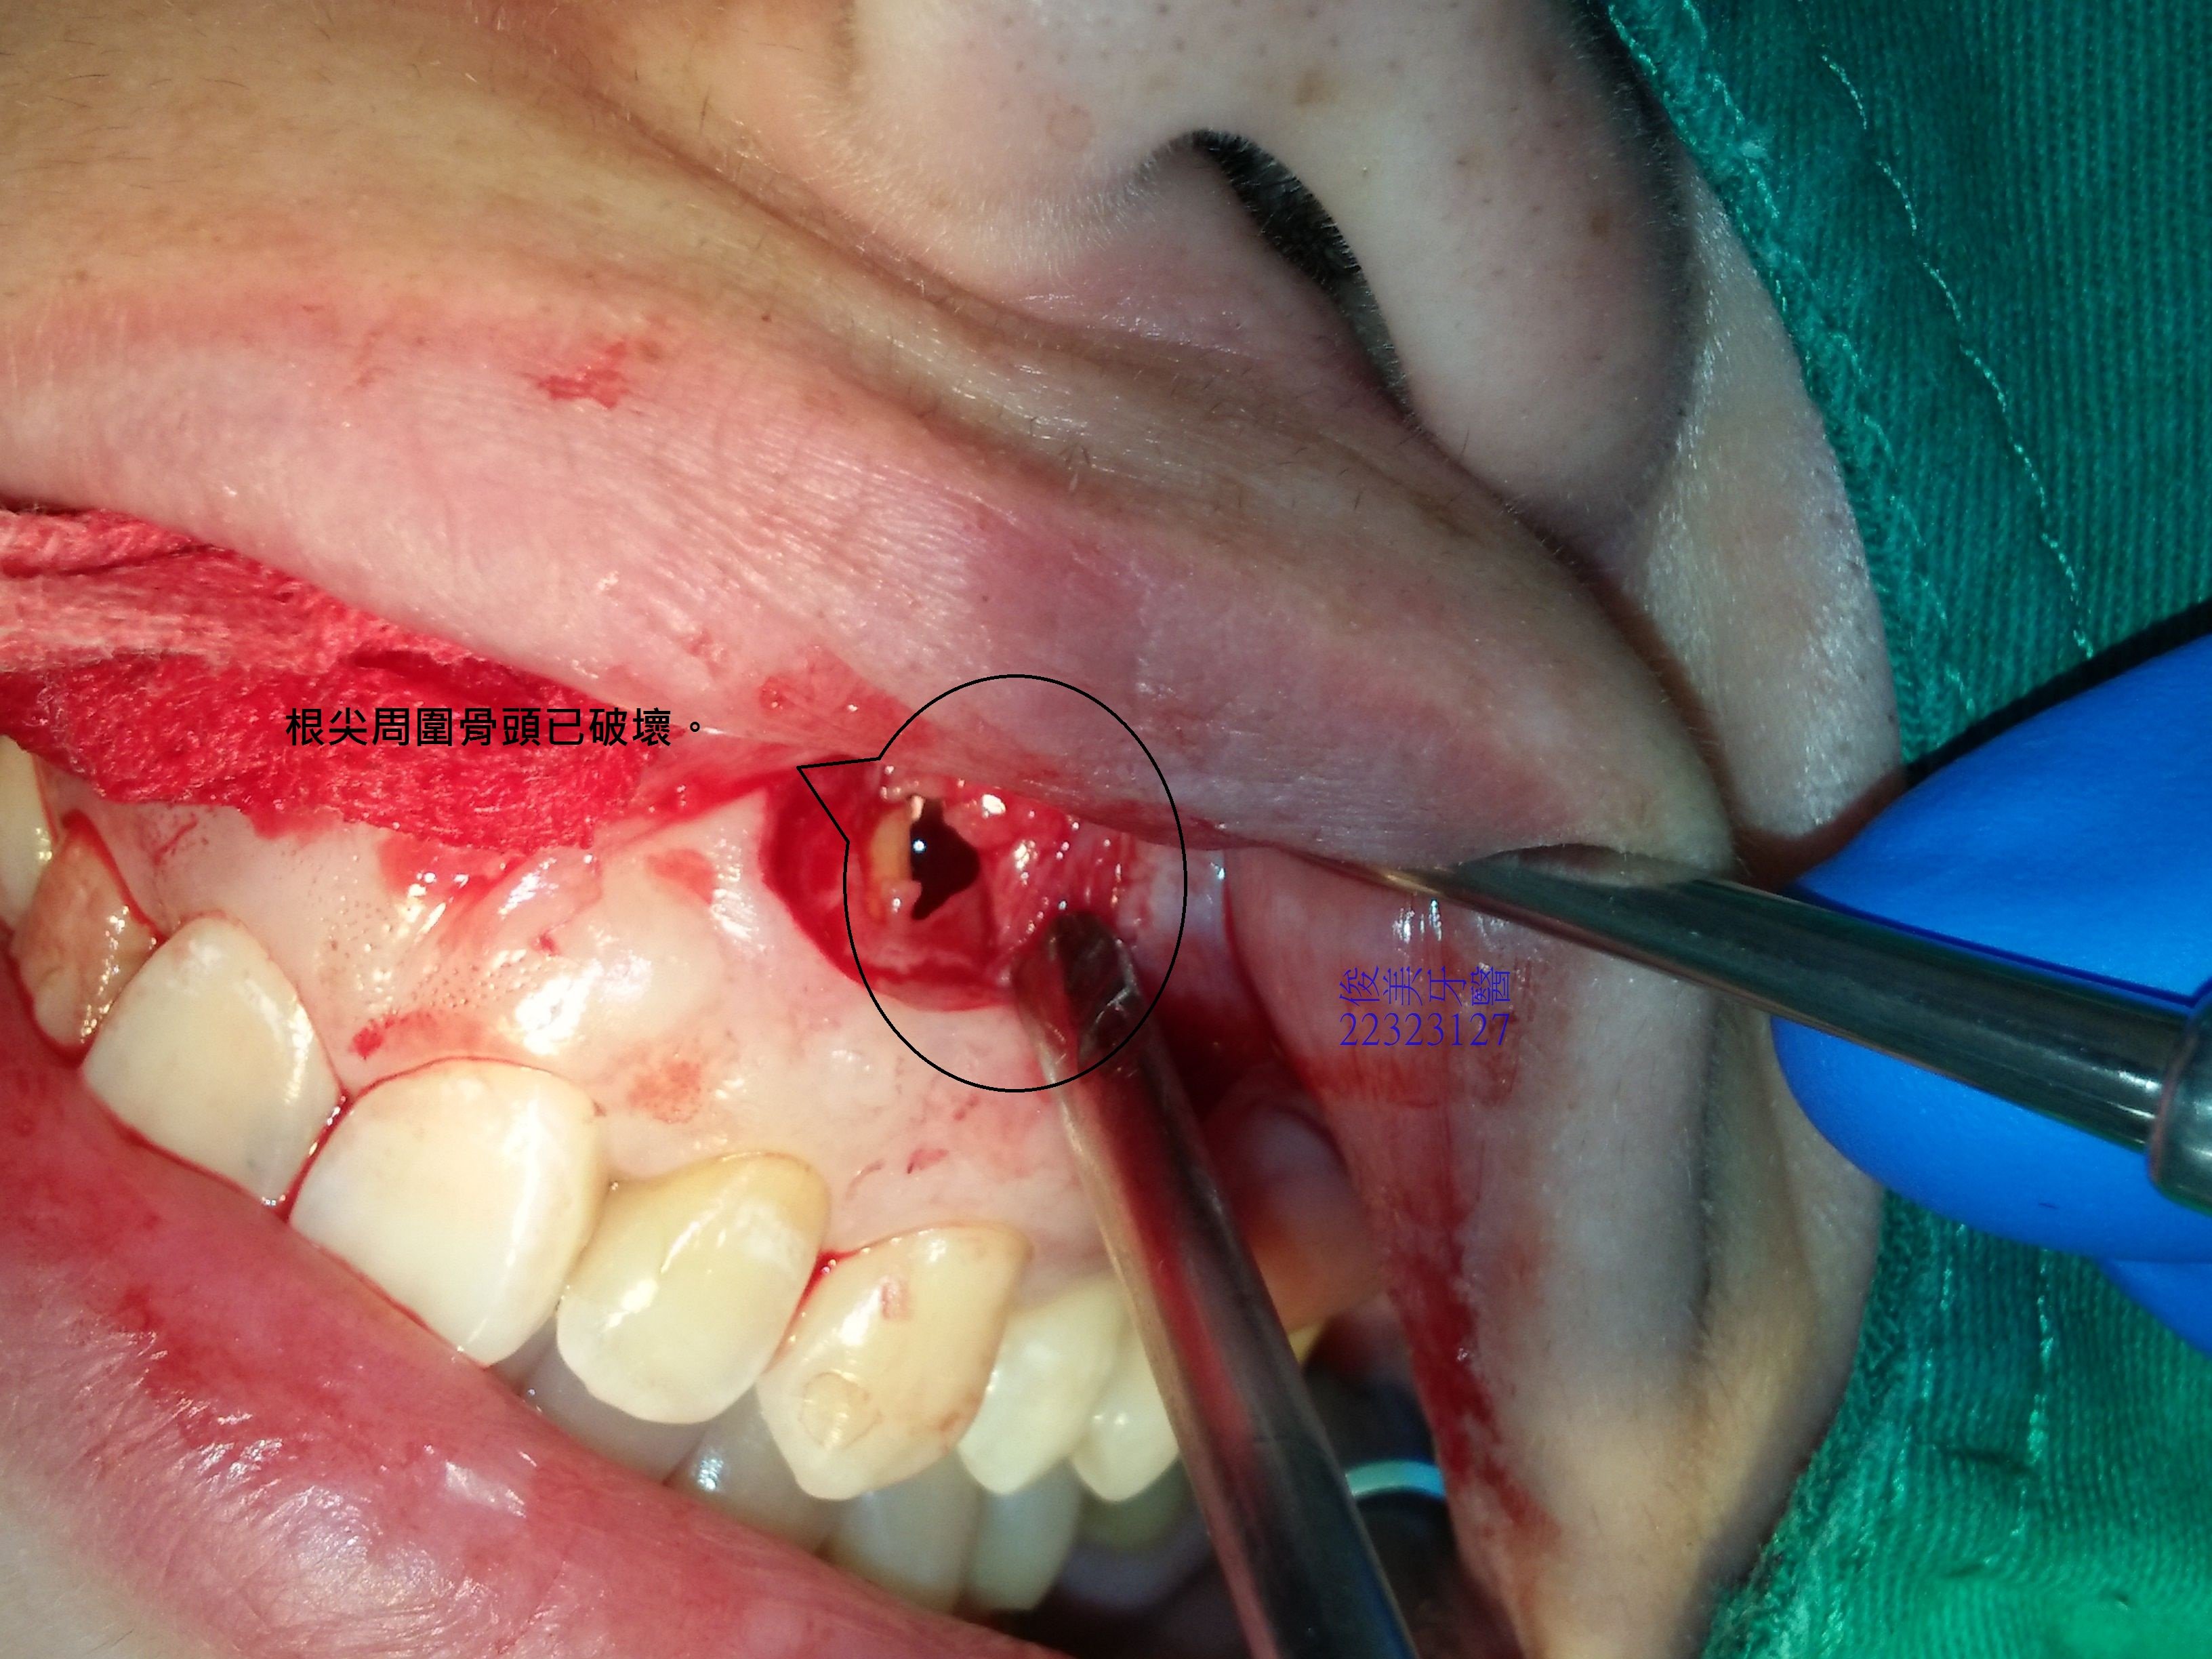

患者左邊根尖打開,明顯可見為空腔,已被細菌破壞。